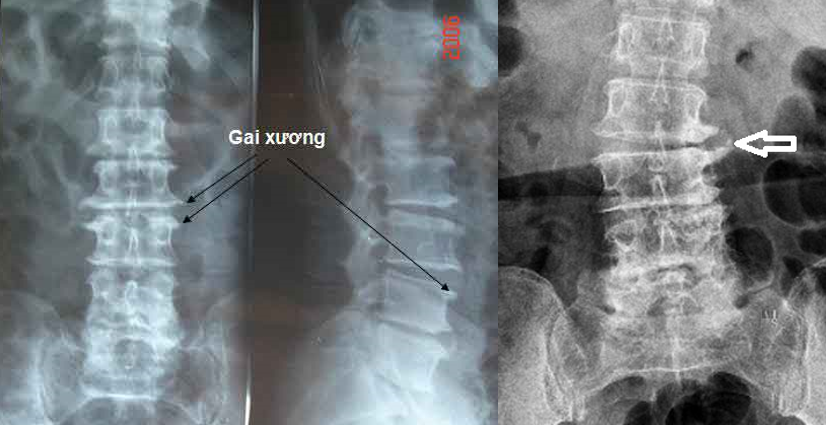

− Xquang thường quy cột sống thẳng, nghiêng: hình ảnh hẹp khe đĩa đệm, mâm đĩa đệm nhẵn, đặc xương dưới sụn, gai xương thân đốt sống, hẹp lỗ liên hợp đốt sống. Trường hợp trượt đốt sống có chỉ định chụp chếch 3/4 phải, trái nhằm phát hiện tình trạng gẫy cuống đốt sống “gẫy cổ chó”.

+ Xquang cột sống thắt lưng thường quy (thẳng – nghiêng – chếch ¾ hai bên): hẹp khe khớp với bờ diện khớp nhẵn, đặc xương dưới sụn, gai xương thân đốt sống, hẹp lỗ liên hợp đốt sống.

− Dấu hiệu chèn ép rễ dây thần kinh thường gặp ở thoái hóa cột sống nặng khi những gai xương thân đốt sống phát triển chèn ép vào lỗ liên hợp đốt sống. Cùng với sự thoái hóa đốt sống, đĩa đệm cũng bị thoái hóa và nguy cơ phình, thoát vị đĩa đệm sẽ dẫn tới chèn ép rễ dây thần kinh (biểu hiện đau dây thần kinh tọa).